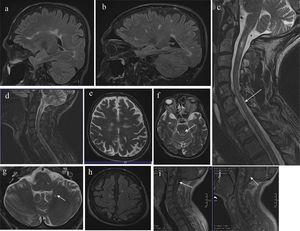

MRI study. (a) and (b) Sagittal FLAIR sequence; (c) sagittal T2-weighted sequence; (d) sagittal STIR sequence; (e–g) axial T2-weighted sequence; (h) axial FLAIR sequence; (i) and (j) gadolinium-enhanced T1-weighted sequence.

Images show hyperintense lesions in the subcortical, juxtacortical, and periventricular white matter; and lesions in the corpus callosum and callososeptal interface, pontomesencephalic junction, pons (←), spinal bulb, and cerebellum (←). Mild cortico-subcortical atrophy is observed. Multiple spinal cord lesions of differing sizes are shown, affecting practically all levels, with a large lesion at the C2 level, mainly on the right side. The thoracic spine (←) displays lesions at T1–T2, T5–T6, T7–T8, T9–T10, and T11. Lesions in the bulbar region (←) and at C2 (←) present gadolinium uptake.